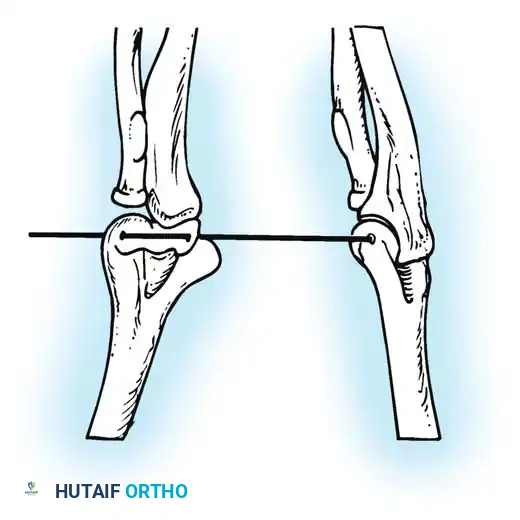

Furthermore, Allende and Freytes identified a pathognomonic radiographic and anatomical feature known as the "radial humeral horn," which was present in 100% of their 35 reported cases.

Fig. 58-23 Anteroposterior radiograph showing lateral dislocation and the characteristic horn of ossification. (From Bruce C, Laing P, Dorgan J, et al: Unreduced dislocation of the elbow: case report and review of the literature, J Trauma 35:962, 1993.)

This "horn" is the direct result of the ossification of a fracture hematoma trapped between the stripped periosteum and the joint capsule near the radial head. Recognizing this structure preoperatively is critical, as it must be surgically excised to achieve concentric reduction.